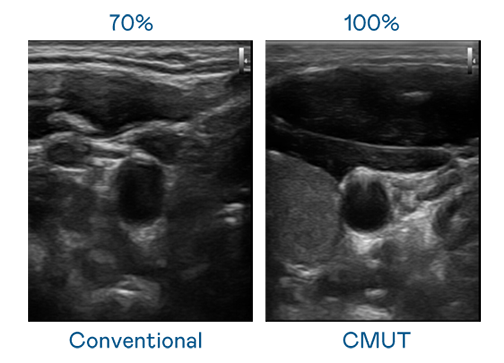

CMUT 技術是一種用電容式微機電元件來產生超音波訊號的技術。與傳統 PZT 壓電式技術相比,CMUT 頻寬增加 30%,更寬頻的超音波訊號讓影像解析度大幅提升,是實現高影像品質醫療超音波掃描、促進精準醫療發展的關鍵技術。

大頻寬帶來超清晰影像超音波影像的解析度高低,首先取決於探頭能發出的訊號頻寬。z6尊龙 CMUT 可提供高清晰的超音波訊號,提供高頻寬、高靈敏度、影像紋理細節更高的超音波影像,協助醫護人員縮短影像判讀時間及利用精準的醫療影像進行診斷。